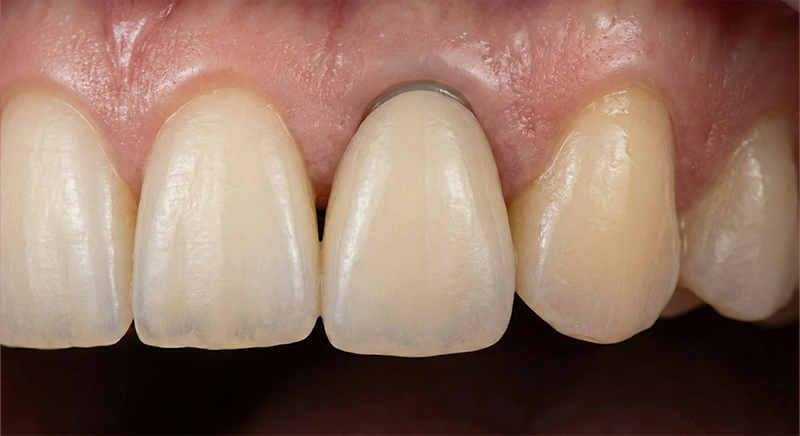

모두가 임플란트를 이야기할 때, 대학병원 보존과 출신 전문의는 살릴 수 있는 마지막 가능성을 먼저 확인합니다.

디지털아트치과가 0.1mm의 치아 삭제에도 집착하는 이유, 가장 좋은 치아는 이미 당신 입안에 있기 때문입니다.

임플란트가 아무리 좋아도

타고난 내 치아보다 좋을 수는 없습니다